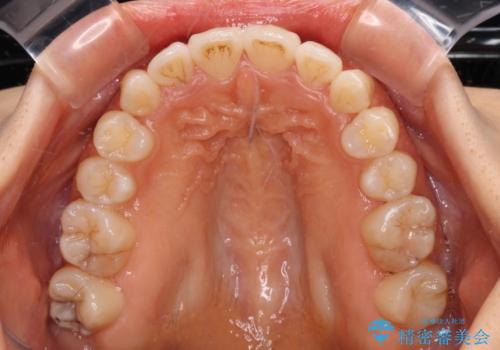

- 飛び出した前歯と口元の突出感を気にして来院された患者様です。

奥歯の咬み合わせを見ると、上顎が下顎に対して相対的に前方にありました。

口元の突出感を改善するためには、上顎臼歯を後方に移動させた咬み合わせにする必要があります。

インビザライン単体で改善することも可能ですが、達成する可能性が高くないため、カリエールディスタライザーという補助装置を併用して、より確実性を上げることとしました。

奥歯の咬み合わせを改善しながら、並行してインビザラインで歯列を整えることとしました。

カリエールディスタライザーを併用したことで、確実かつ短期間で治療を終えることができました。